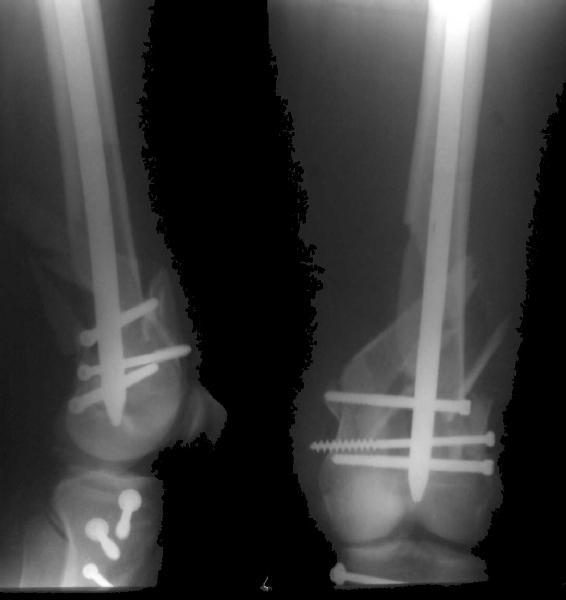

Отправитель: Zsolt Balogh 31 Октябрь 2004, 12:13

This is what we have done... As generally true for LISS look at the bone not the hardware.

There are two more srews above. The one not completely in got damaged head.